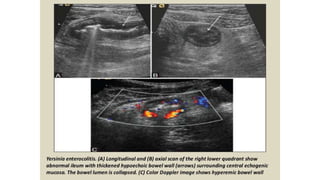

This document discusses the evaluation of right lower abdominal pain and lists appendicitis as a key cause. It notes that other potential causes include hemorrhagic cysts, heterotrophic pregnancy, salpingitis with pyosalpinx, funiculitis, and torsion of an undescended testis. The document was presented by Dr. A.S.M. Sufian of Cumilla Medical College Hospital and thanks the audience for their patience and listening.